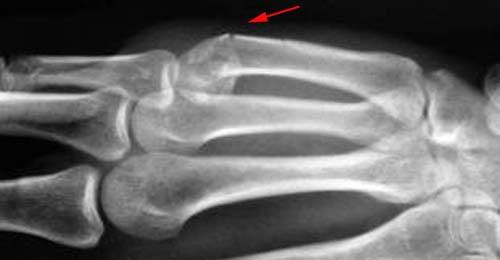

Диагностика переломов пястных костей

Любая значимая травма кисти нуждается в осмотре травматолога и рентгенографии. Пациент может подумать, что это ушиб, но возможен перелом, например, ладьевидной кости, которая может создать очень много проблем. Банальная рентгенография не займет много времени, но пациент уже будет точно знать ушиб это или перелом.

Осмотр травматолога: обследование может выявить видимые деформации, если перелом с явным смещением. Если смещение небольшое или его вовсе нет, анатомия кисти может и вовсе быть нормальной. Локальный отек и болезненность при пальпации (прикосновении) будет в проекции перелома. Возможно снижение силы хвата.

Так же при осмотре врач обращает внимание на возможную ротацию пальцев (поворот вокруг оси). Оценить этот момент можно при сгибании пальцев в кулак. Пальцы должны выстроиться в ряд без разворота и ногти должны быть параллельными.

Инструментальные методы обследования:

Рентгенография. Для диагностики перелома пястной-(ых) кости выполняется рентгенография в трех проекциях: прямой (переднезадней), боковой (сагиттальной) и косой (3/4).

КТ (компьютерная томография) используется в сложных случаях, когда перелом многооскольчатый или внутрисуставной, а так же для подтверждения диагноза несращения перелома.